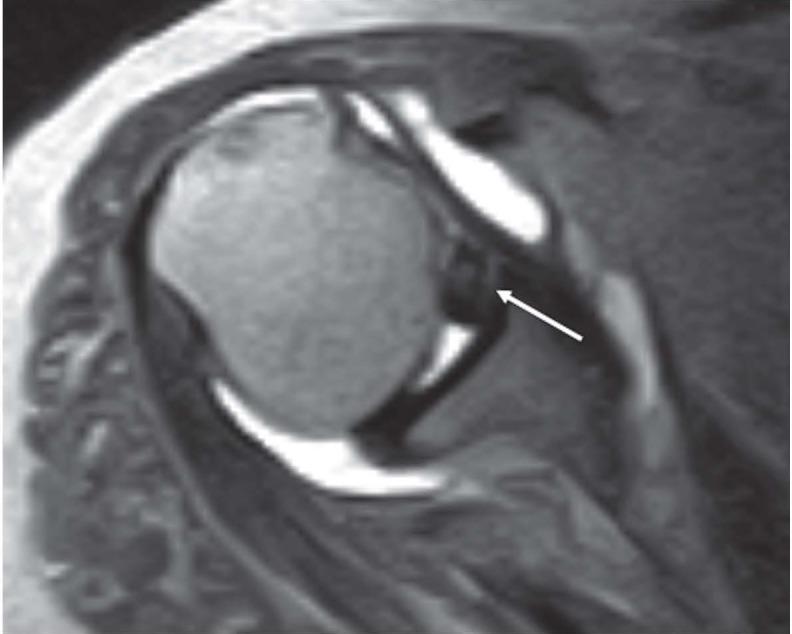

The aim of this is article is to provide an  imaging review of normal anatomy, most common anatomical variants and pathologies of the long head of the biceps tendon (LHB) encountered during the daily practice.

本文的目的是对日常实践中遇到的肱二头肌长头肌腱(LHB)的正常解剖结构、最常见的解剖变异和病变进行影像学综述。